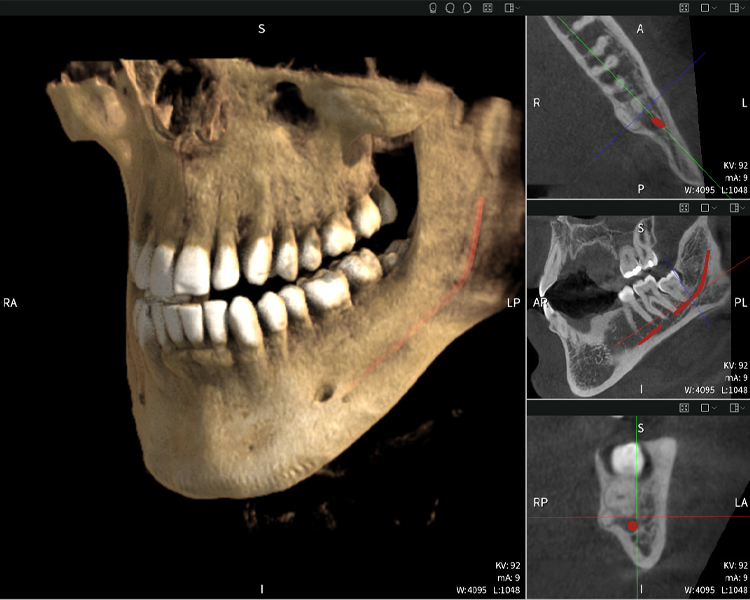

Below you will find a case from Dr. med. dent. Oliver A. Centrella, in which the CBCT images obtained with Seethrough Max provided crucial information on the complex anatomy and the critical relationship between the wisdom teeth and the inferior alveolar nerve. In this case, there is a indication for the surgical removal of the wisdom teeth.

Figure a

- Top left: Axial cross-section of the left mandible (region 38) showing the inferior alveolar nerve (red) in proximity to the roots of tooth 38.

- Top right: 3D reconstruction of the entire mandible for orientation. The red-marked inferior alveolar nerve illustrates its location within the jawbone.

- Bottom left: Sagittal view of the mandible (region 38), highlighting the close spatial relationship between the roots and the nerve canal.

- Bottom right: Coronal view of the mandible (region 38), which is crucial for assessing the spatial position of the roots relative to the nerve.